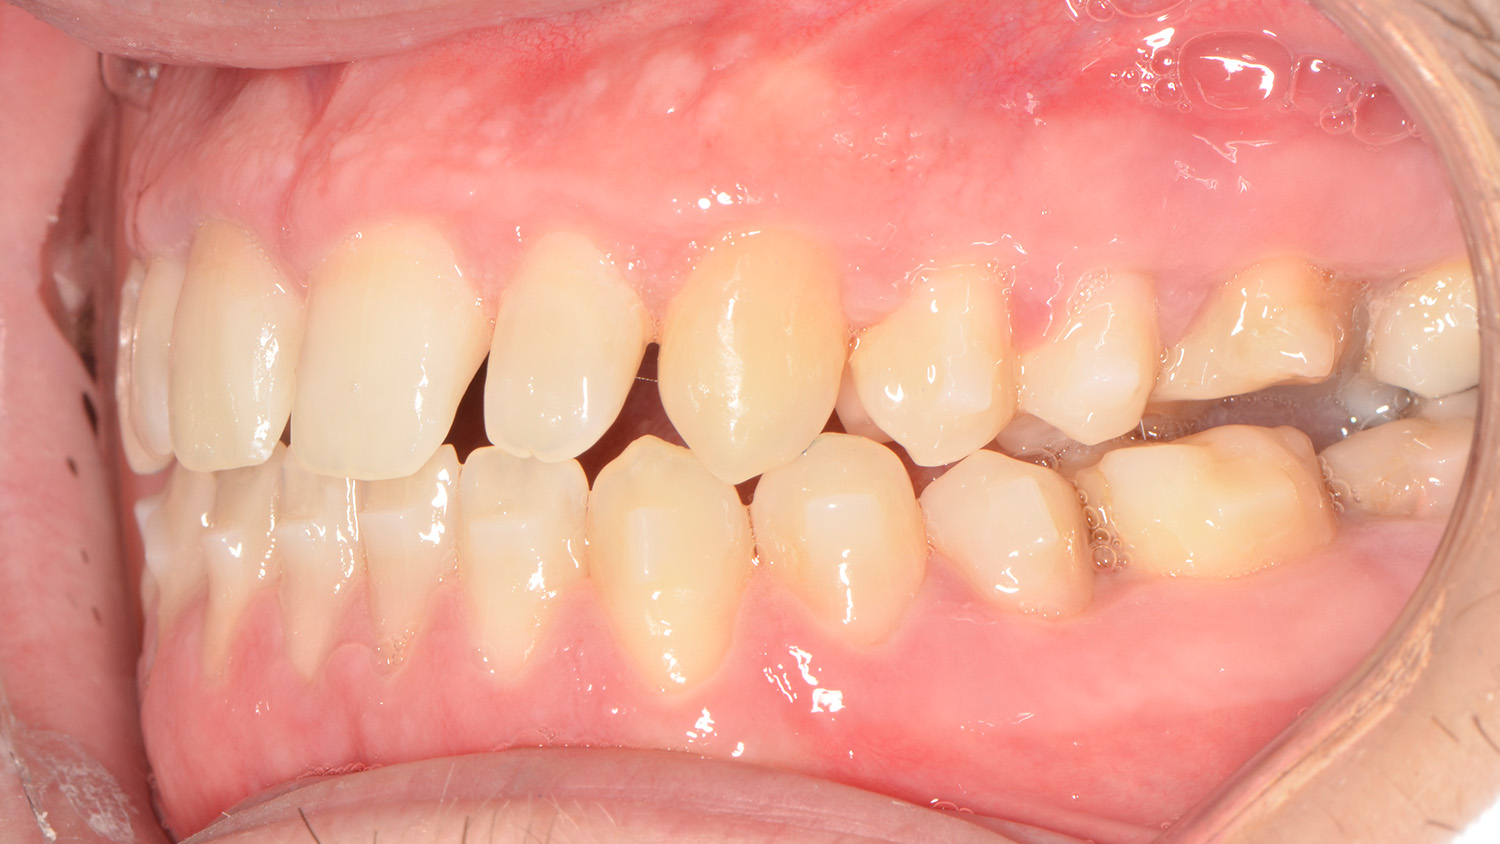

Intraoral examination showed an Angle Class III relationship on both sides, along with an anterior open bite. Additionally, a narrow maxilla with a bilateral posterior crossbite was observed.

The primary goal of the treatment was to correct the transverse deficiency of the maxillary arch (>5 mm) and resolve the skeletal crossbite. MARPE was used to address this transverse issue.

Once the transverse discrepancy was corrected, treatment continued with Spark Aligners to address the vertical plane. The planned vertical correction involved extruding the upper anterior teeth, with 1.7 mm of extrusion in the upper arch, and 1.5 mm in the lower arch using attachments. To assist in bite closure, turbo bites were employed to intrude the mandibular molars.

As shown in the accompanying images, the planned vertical correction was fully achieved. At this stage, provisional composite veneers were placed from canine to canine in the upper arch to enhance the patient’s aesthetics and compensate for Bolton’s discrepancy.